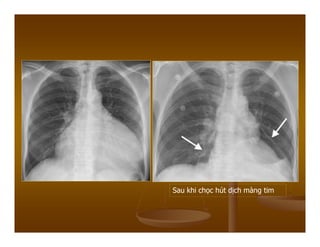

Following pericardial tap and air

injection air-fluid level (large

arrow),true cardiac border

(small arrows),note the normal

thickness of the pericardium.

Sau khi chọc hút dịch màng tim

Sau khi chọchút dịch màng tim